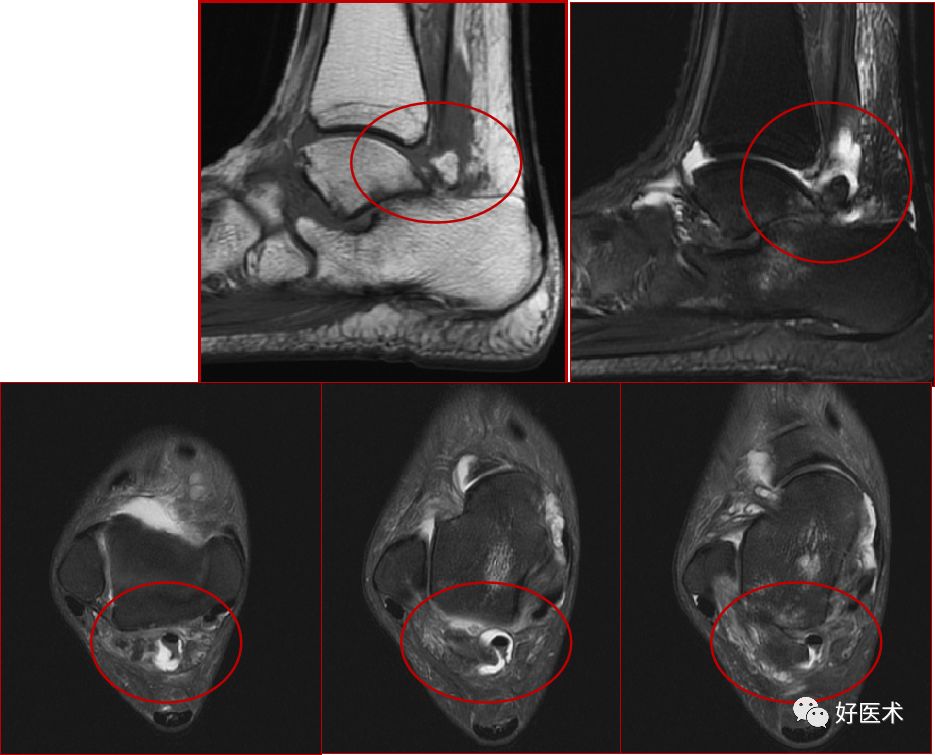

三、骨软骨病变

距骨骨软骨损伤,好发于前外侧、后内侧,尤其是后内侧,与内外翻损伤相关。

距骨骨软骨损伤分级

1度损伤:

2度损伤

3度损伤